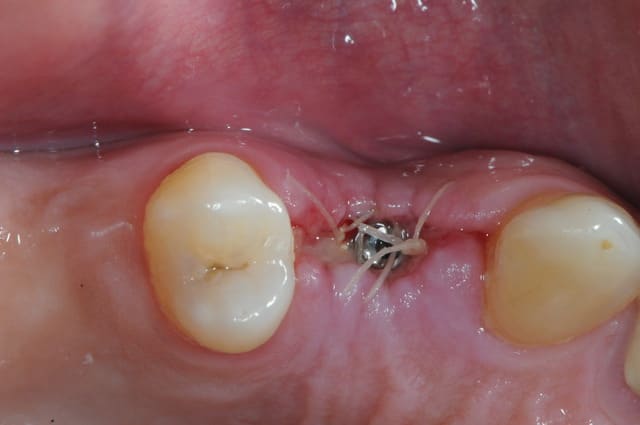

suite..

come ce con de patient fume et picole peut être aussi, il revient à 10 jours avec plusieurs fils de suture de perdu depuis au moins trois jours.

j'explique pourtant longuement aux patients que "si il y a un doute, c'est qu'il n'y a pas de doute"

comprenez, par là que si on pense avoir perdu un fil, j'incite les patients à venir IMMEDIATEMENT et sans RDV.

bref, cet imbé%$µ?"# se pointe et me dit que ça gène un peu.

tu parles! nécrose osseuse, exposition de l'implant et de la crête osseuse photo 1 et 2

donc pince gouge pour l'os "mort" cruantage de berges gingivales, irrigation, sutures bref, je fais le pompier de service.

photo 3: contrôle à 4 jours, le plus grave est passé!

n’empêche que les dégâts sont considérables...la tête de l'implant est exposée.

aujourd'hui donc...

je revois le patient, l'implant est bel est bien supra crestal et la prothèse va donc être impossible à gérer.

d'autant plus que les piliers sont des piliers platform switching ce qui va rendre ceux ci complètement visibles.

bref, je prends la décision de soit explanter soit implanter plus profond.

c'est la deuxième solution que je retiens car l'os du patient était extrêmement mou ( type 4).

j'ai même pas eu d'efforts à faire pour pousser(visser) l'implant un peu plus loin!!!

bon j'ai oublié de faire une photo post op, mais je suis sure que vous me pardonnerez, c'est le week end après tout non ?